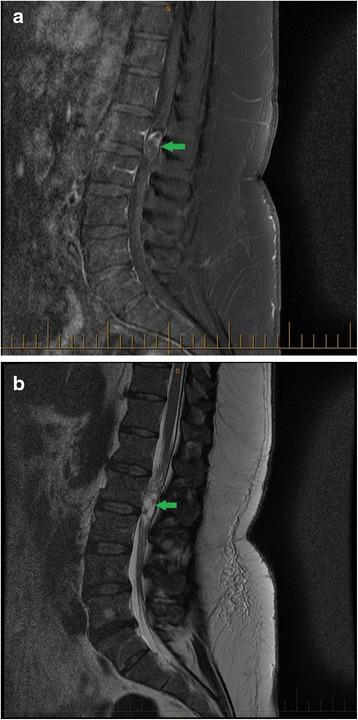

A 48-year-old male police officer was referred to a chiropractic clinic by a general practitioner for the evaluation of recurrent acute low back pain (LBP). Although the first episode of LBP was resolved, the clinical examination during the second episode revealed subtle changes that warranted referral to magnetic resonance imaging (MRI). The MRI revealed a spinal myxopapillary ependymoma.

一名48岁男性警官因复发性急性下腰痛(LBP)被全科医生转诊至一家整脊诊所。尽管首次LBP发作已缓解,但第二次发作时的临床检查发现了细微变化,这使得转诊进行磁共振成像(MRI)检查成为必要。MRI显示为脊髓黏液乳头型室管膜瘤。